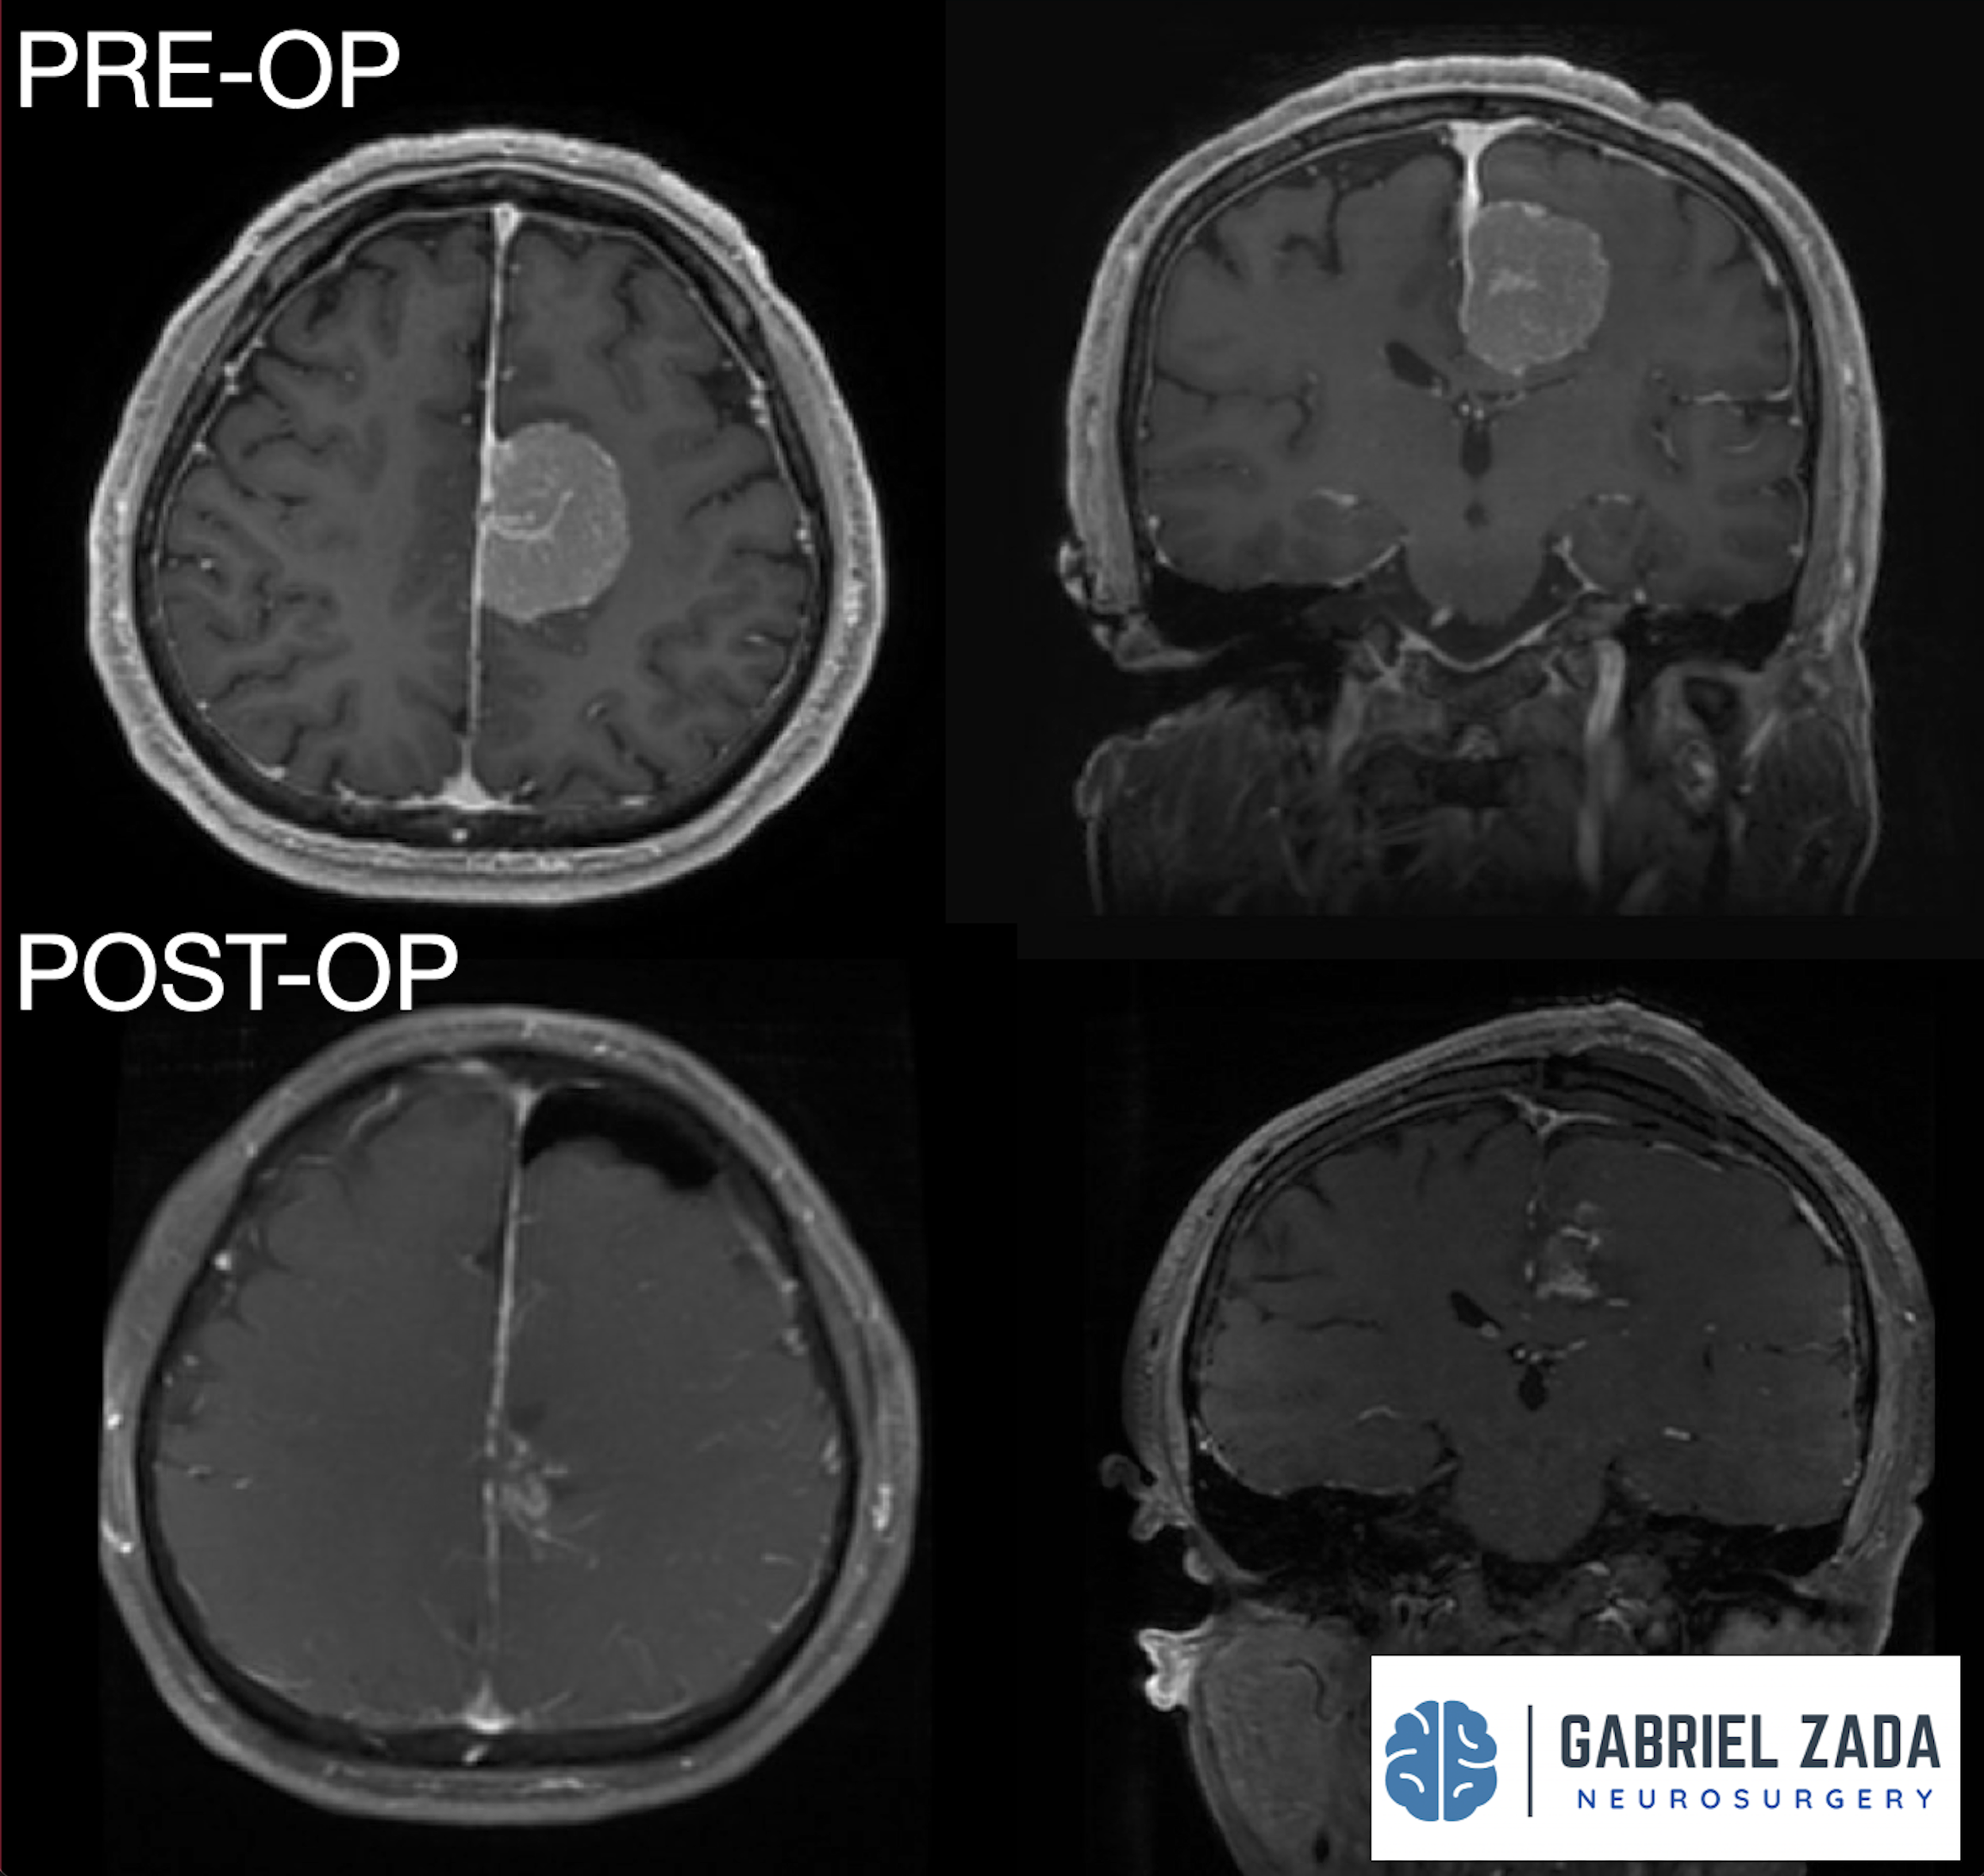

Explore this comprehensive gallery featuring pre‑ and post‑operative imaging of patients with skull‑base tumors treated by Gabriel Zada, MD, MS, FAANS, FACS. These cases highlight Dr. Zada’s expertise in advanced neurosurgical techniques and outcomes.

*Representative cases shown for educational purposes. All images de-identified. Individual results vary.